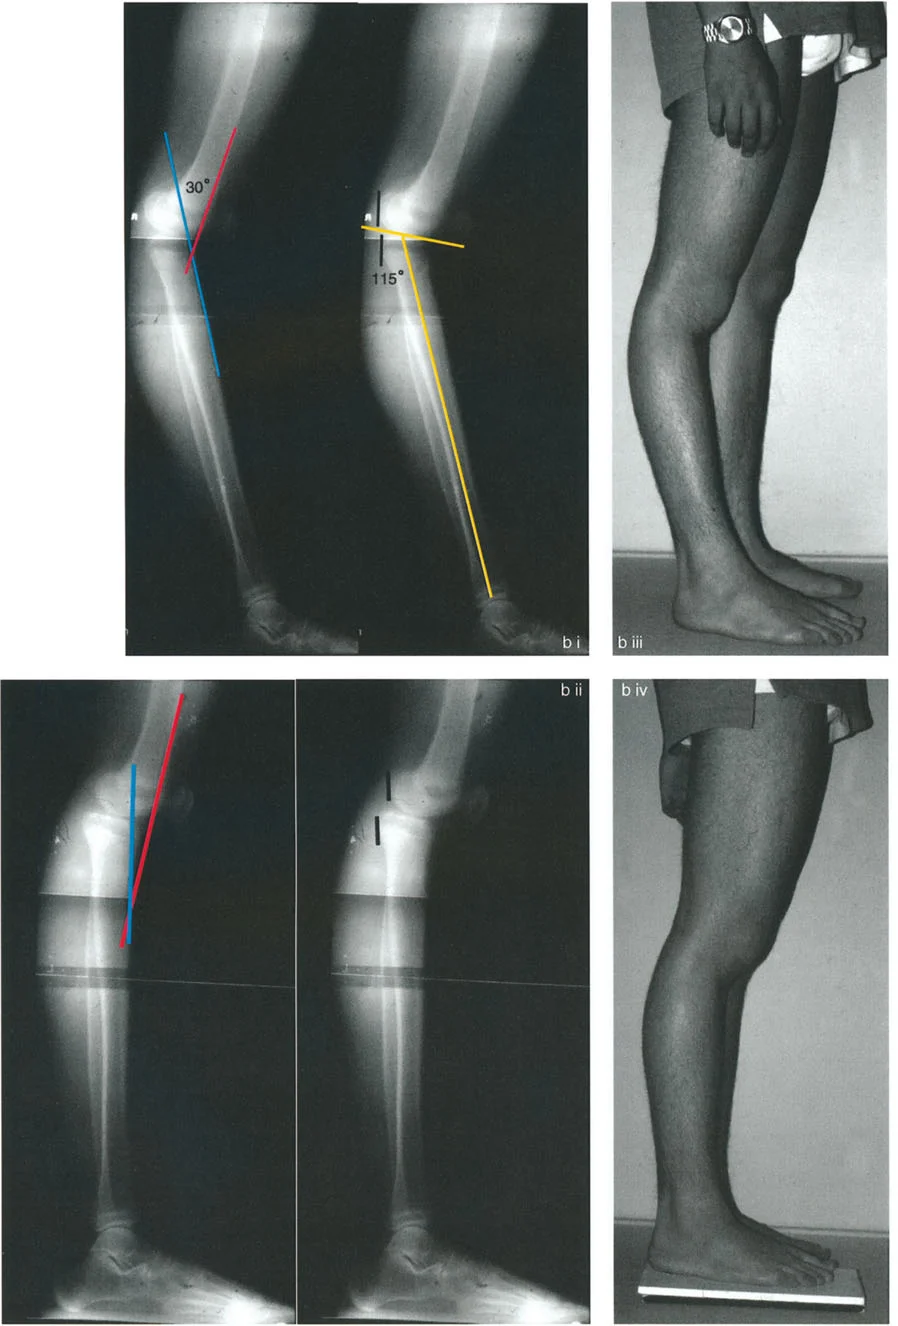

الارتداد الظنبوبي (Tibial Recurvatum):

- ينتج عن انحناء مفرط في الجزء العلوي من عظم الساق (الظنبوب)، مما يدفع الركبة إلى التمدد الزائد.

- يمكن أن يحدث بسبب توقف نمو جزئي في عظم الساق القريب، كما هو الحال في بعض حالات الكسور أو العدوى التي تؤثر على صفيحة النمو.

- حالة مريضة تبلغ من العمر 24 عامًا عانت من كسر في الفخذ في سن 12 عامًا، وعولجت بالشد. تسبب دبوس الشد في توقف نمو جزئي في الجزء القريب من عظم الساق، مما أدى إلى ارتداد ظنبوبي.

- تقييم مدى الحركة: يتم قياس مدى حركة الركبة، بما في ذلك أقصى تمدد وأقصى انثناء. يتم تحديد درجة فرط التمدد (HE - Hyperextension) أو درجة تقلص الانثناء الثابت (FFD - Fixed Flexion Deformity).

تُعد الأشعة السينية ضرورية لتقييم التشوهات العظمية في المستوى السهمي. يتم التقاط صور شعاعية جانبية (Lateral X-rays) للركبة في وضعيات مختلفة (تمدد كامل، انثناء).

- زاوية الانحناء البعيدة للفخذ (PDFA - Posterior Distal Femoral Angle): تقيس زاوية الجزء السفلي من عظم الفخذ. القيمة الطبيعية حوالي 84 درجة. الزيادة في هذه الزاوية (أكثر من 84 درجة) تشير إلى ارتداد فخذي.

- زاوية الانحناء القريبة للظنبوب (PPTA - Proximal Posterior Tibial Angle): تقيس زاوية الجزء العلوي من عظم الساق. القيمة الطبيعية حوالي 80 درجة. الزيادة في هذه الزاوية (أكثر من 80 درجة) تشير إلى ارتداد ظنبوبي.

- الركبة الارتدادية بسبب الارتداد الظنبوبي:

- إذا كانت درجة فرط التمدد (HE) تساوي درجة الارتداد الظنبوبي (PPTA > 80°)، فهذا يعني أن التشوه كله ناتج عن عظم الساق.